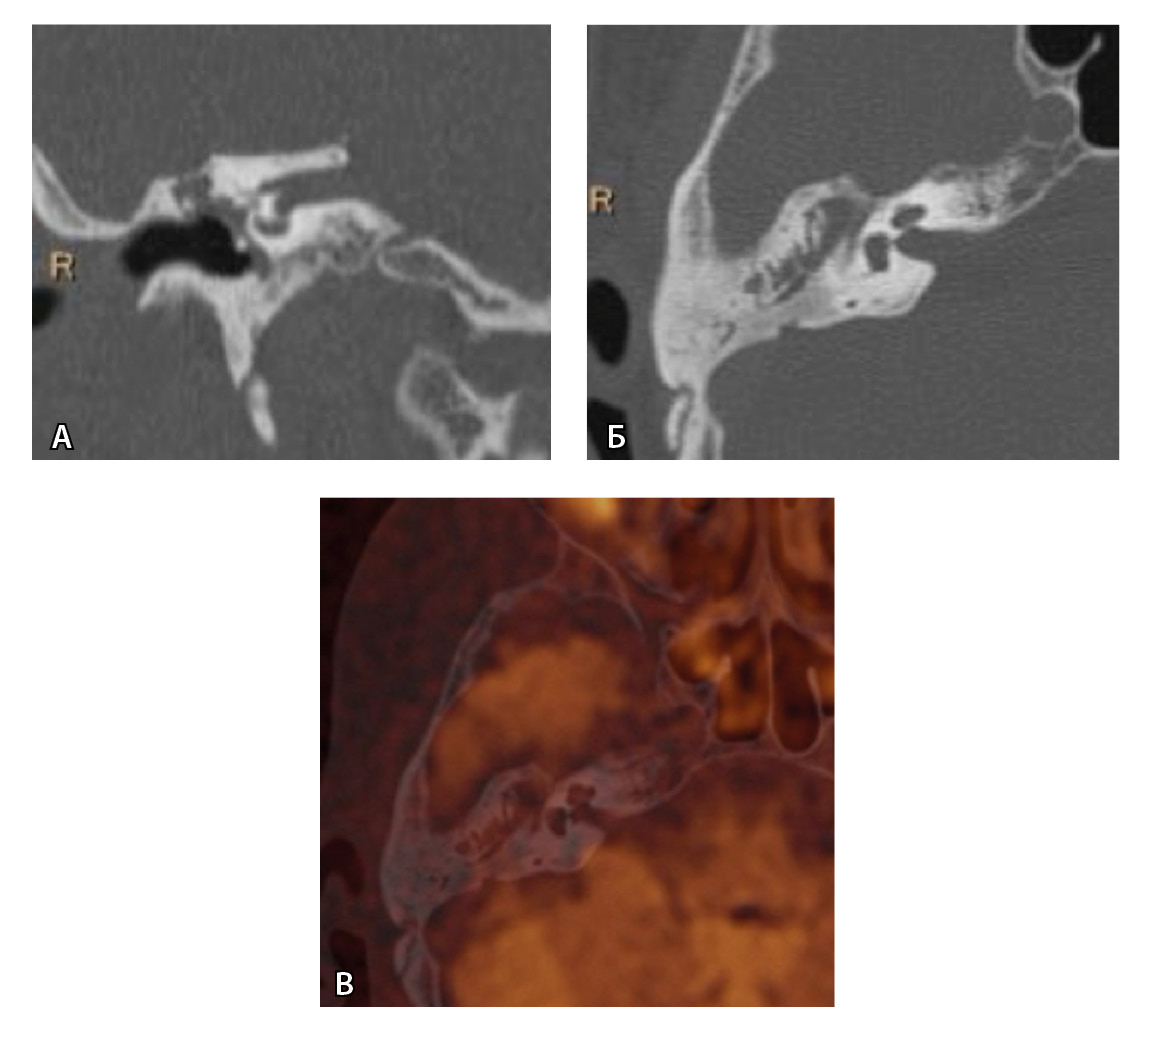

Рис. 3. Хронический правосторонний средний отит. По данным компьютерной томографии (А, Б) нет ремоделирования барабанной полости, деструкции и смещения косточек, скутум сохранен, данных за холестеатому нет. При магнитно-резонансной томографии (В, Г) у того же пациента выявлен очаг высокого магнитно-резонансного сигнала, который при слиянии локализовался в области пространства Пруссака. Заключение и интраоперационно – холестеатома пространства Пруссака

Рис. 4. При компьютерной томографии (КТ) визуализируются признаки хронического гнойного среднего отита справа. Наблюдаются латерализация косточек среднего уха и узурация их по имедиальной поверхности на уровне эпитимпанума (тело наковальни и головка молоточка) – классические КТ-признаки холестеатомы натянутой части барабанной перепонки (А, Б). Однако по данным магнитно-резонансной томографии (В) и в последующем при оперативном лечении холестеатома не подтверждена